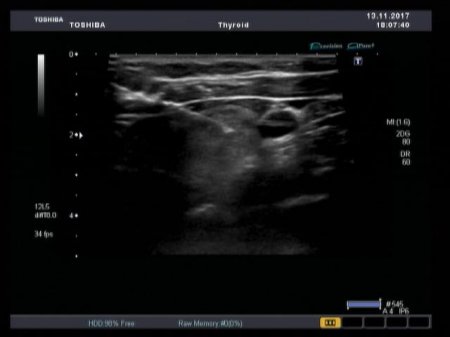

– линейным (для поверхностных органов),

Precision Imaging (Прецизионная визуализация) ультразвуковой системы Aplio позволяют получать более реалистичные изображения и обеспечивает высокую степень послойной дифференцировки тканевых структур и анатомическую точность в визуализации деталей.

Режим дифференцированной тканевой гармоники (DTH) обеспечивает высокую детализацию глубоко расположенных структур. Поскольку в этом режиме за один импульс передаются сигналы на двух различных частотах, изображения обладают непревзойденным пространственным разрешением и контрастностью, а также большей глубиной проникновения.

Технология «компрессионной эластографии» с функцией сохранения исходных “сырых” данных предназначена для локализации и оценки жесткости пальпируемых образований. Количественно

оценивается различная степень жесткости выбранных областей, или же получаемые изображения кодируются цветом с последующим количественным анализом в относительных величинах.